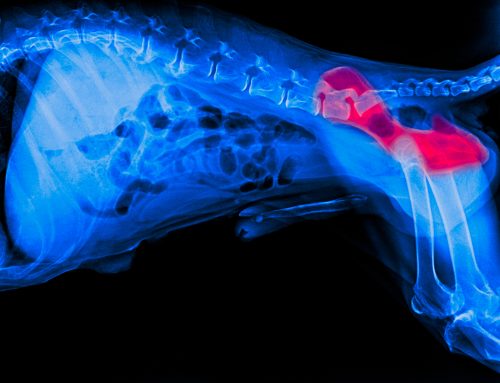

Spays and Neuters are routine surgical procedures that prevent pets from reproducing. Spaying is the term used for female pets and involves the removal of the ovaries and uterus. Neutering, on the other hand, refers to the procedure performed on male pets, which involves the removal of the testicles.Â

* Cancer Prevention: Spaying drastically reduces the risk of mammary (breast) cancer, especially when performed before the first heat cycle. It also eliminates the risk of uterine infections and tumors. Neutering significantly reduces the risk of testicular cancer in male pets.

* Improved Overall Health: These procedures can also minimize the risk of other reproductive health issues, such as pyometra (a life-threatening uterine infection) in females and certain prostate issues in males.